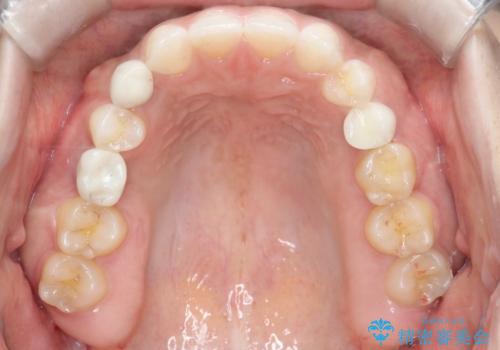

- 後続永久歯が欠損した患者様です。

矯正治療にて歯並びを改善したのち、インプラントにて咬合回復を行う治療計画としました。

捻転が強い部分だけはワイヤーの部分矯正で対応しております。